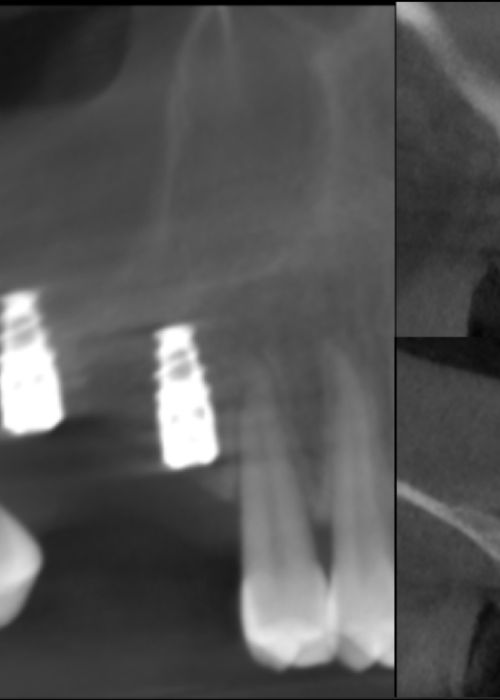

Evolución de un implante migrado al seno maxilar tras rehabilitación con carga inmediata